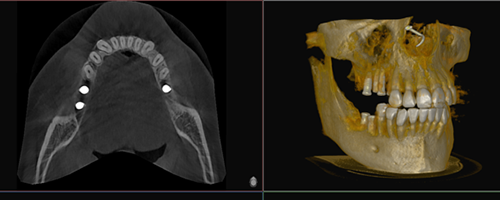

Bei biadent verbinden wir fortschrittliche Behandlungsmethoden mit höchster handwerklicher Präzision. Durch den Einsatz neuster Technologien garantieren wir Ihnen eine diagnostisch fundierte und therapeutisch exzellente Versorgung.